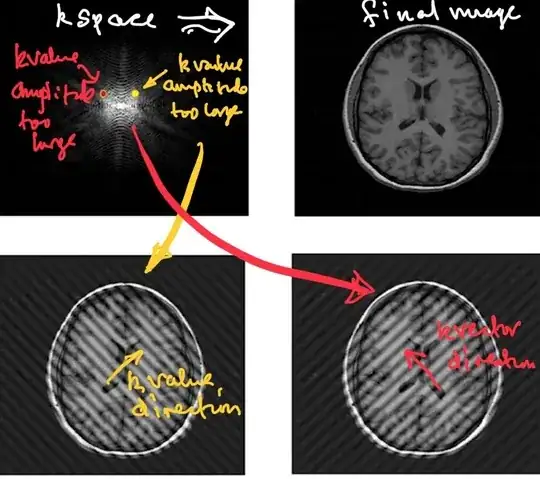

Each point in physical space (patient) will contribute one frequency component to the time domain signal. Conversely, each point in k-space represents the magnitude of one given spatial frequency over the whole image.